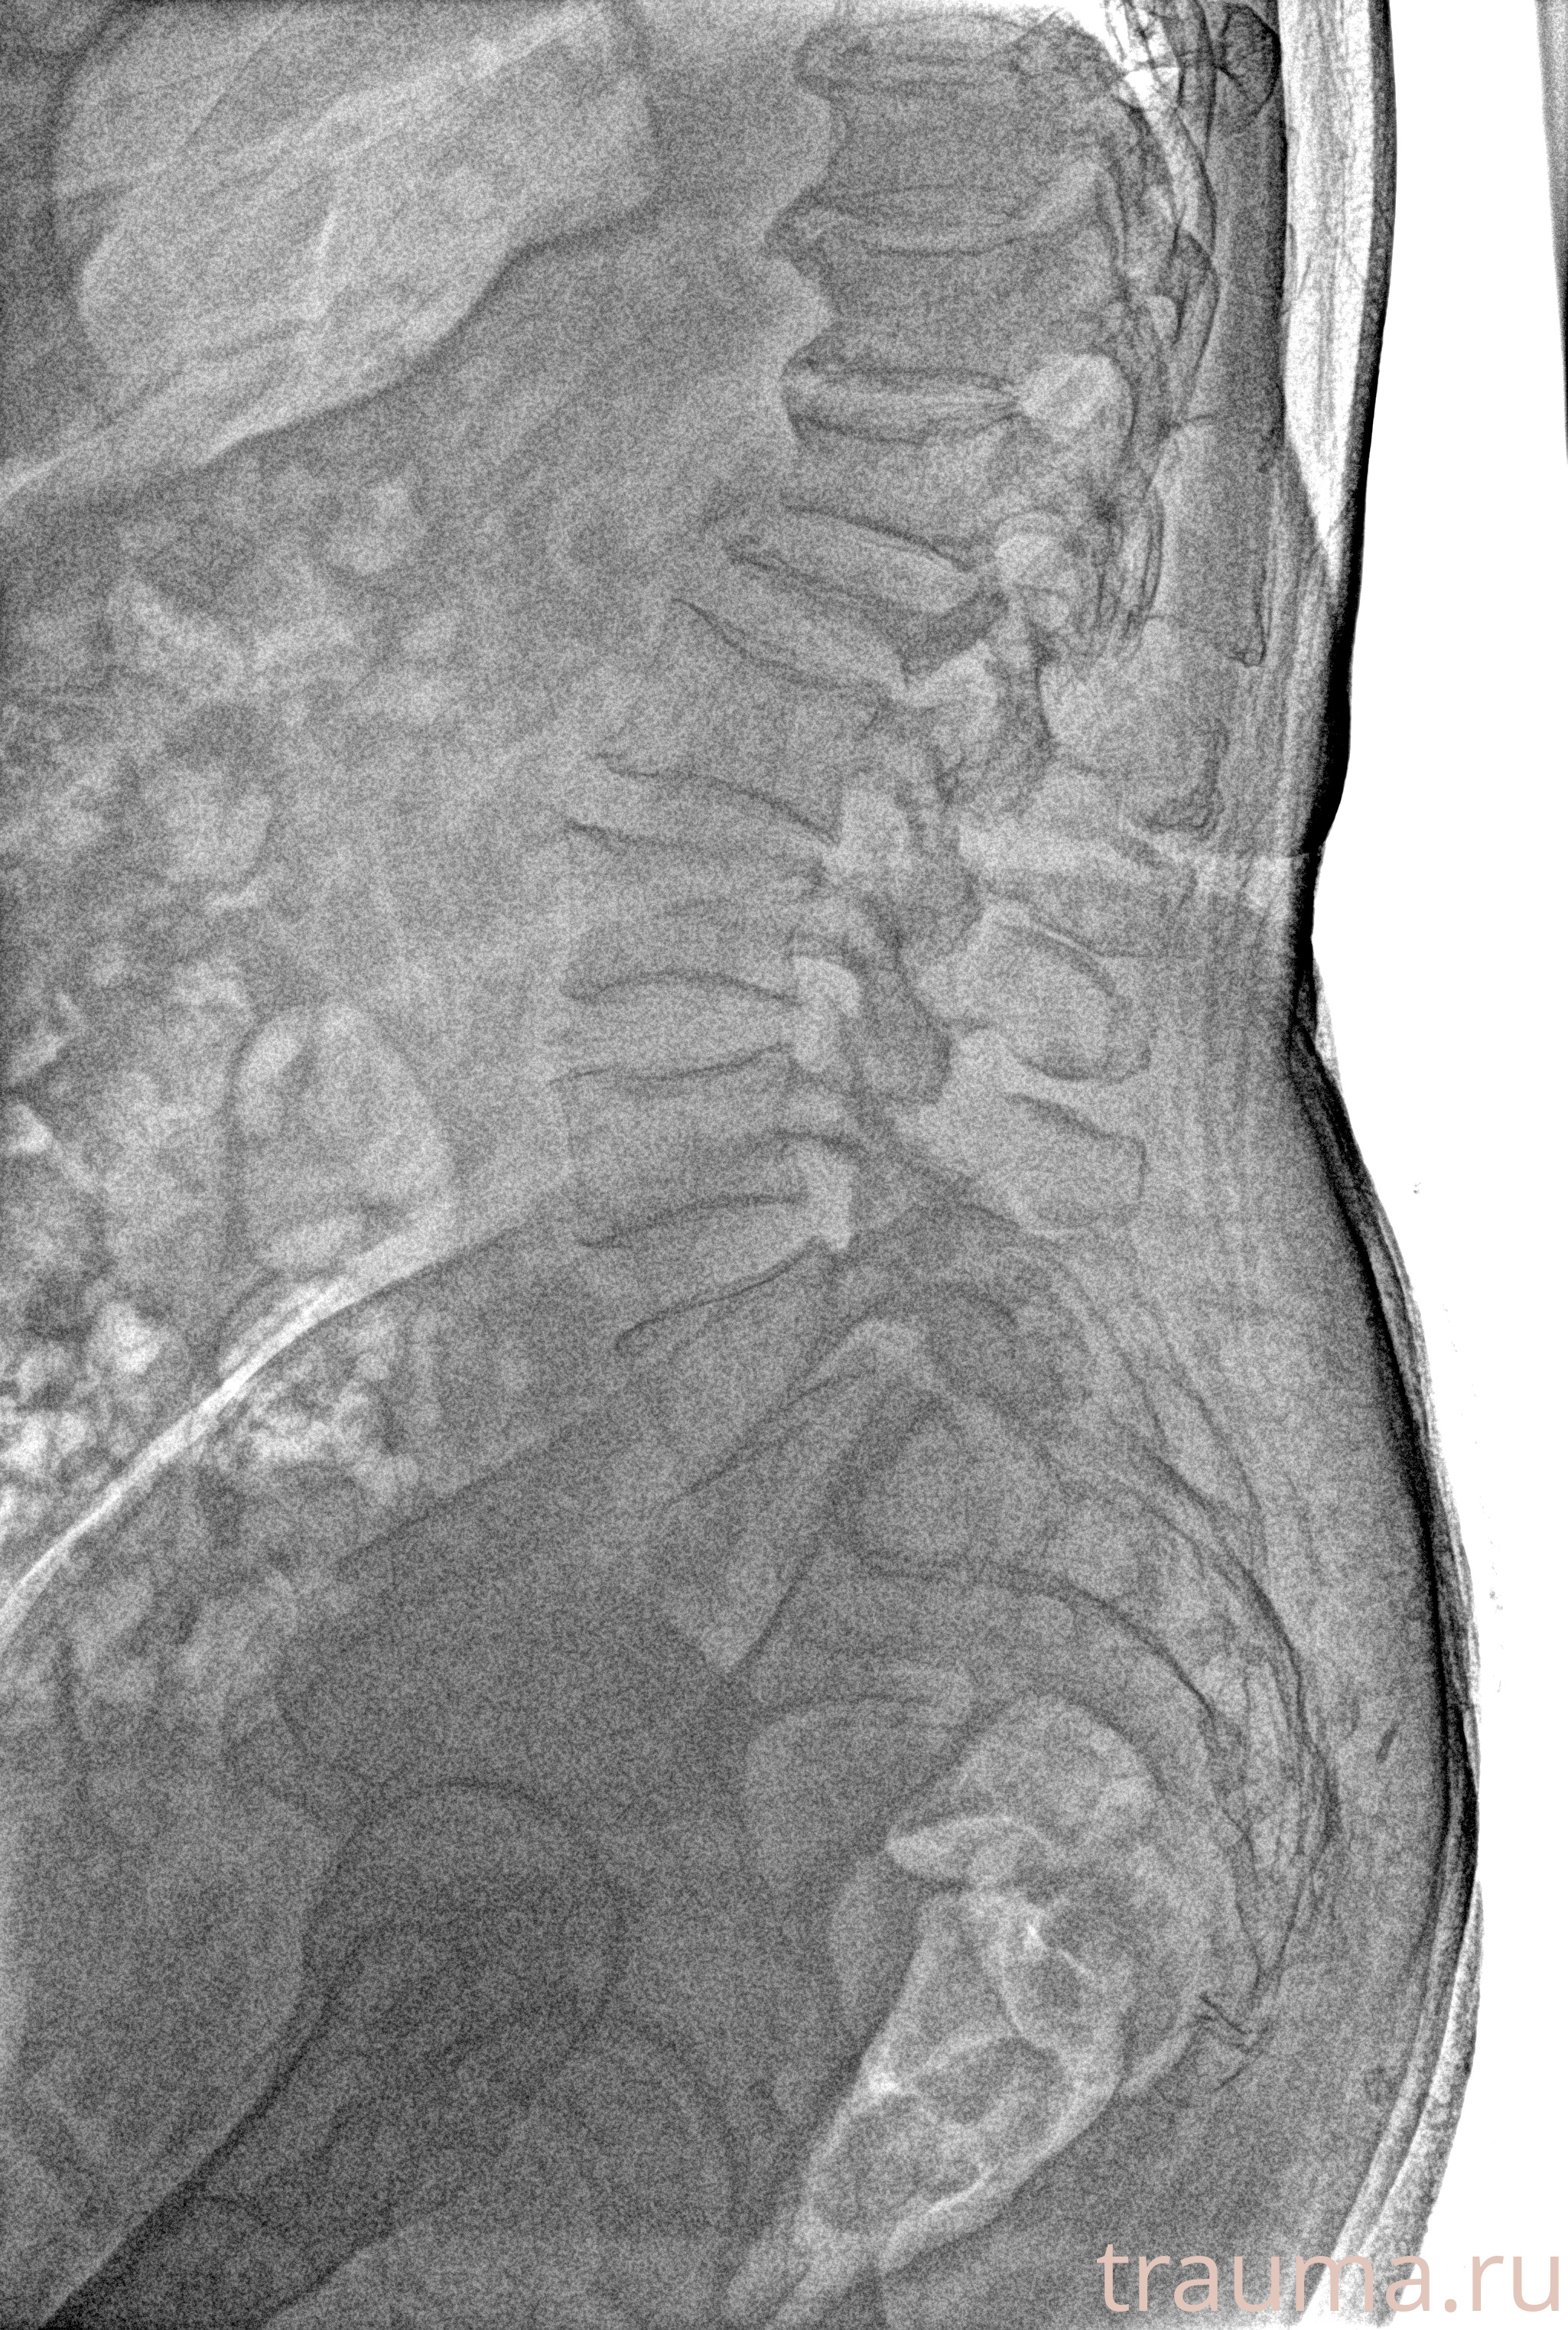

Рентгенограммы

Рентген на дому: по вашему адресу приезжает врач-рентгенолог, травматолог-ортопед с мобильным рентгеновским аппаратом, проводит диагностику травмы или заболевания, делает необходимые рентгенограммы, дает рекомендации по дальнейшему лечению. Получить качественные снимки в домашних условиях возможно благодаря уникальной методике, разработанной МосРентген Центром для института  Склифосовского